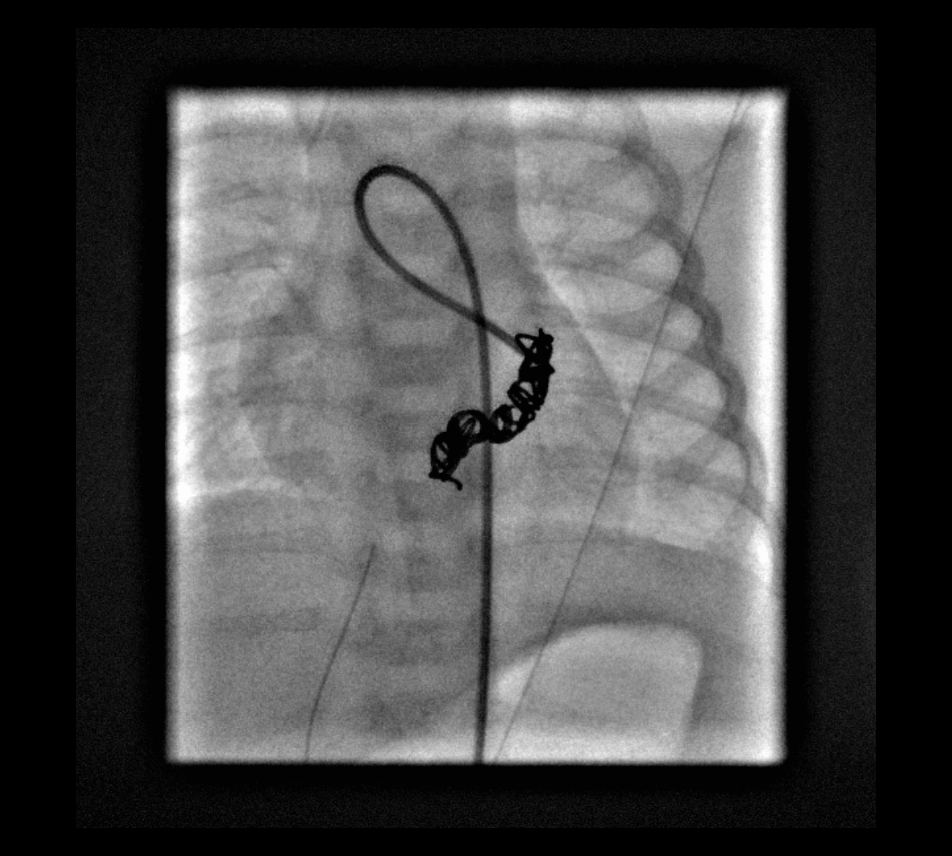

Coronary angiography revealed the fistulous connection to the coronary sinus off of the distal left circumflex coronary artery (LCX). Embolization of the fistula was performed using 2 coils (14 cm × 4 mm distally and 14 cm × 6 mm proximally). Repeated coronary angiography results confirmed the complete occlusion of the fistula and good filling of the left coronary artery (Figures 1-6, fluoroscopic anteroposterior views of the chest).

Figure 5. Fluoroscopic view demonstrating placement of the second embolization coil in the LCX fistula.

Figure 6. Angiogram of the LCX showing no residual shunting through the fistula.